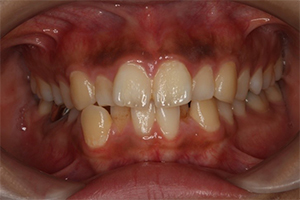

矯正治療のCASE 03

Before

After

- 主訴

- 上下とも歯が出ていて気になる

- 治療内容

- ラビアル矯正(表側)

抜歯あり

- 治療費用

- 88万円~(税込)

- 治療期間

- 18か月

【リスク・副作用】

歯の痛み、口内炎、歯磨きがしにくいことによるむし歯や歯周病のリスク、歯根吸収や歯の変色、後戻りなどの副作用があります。